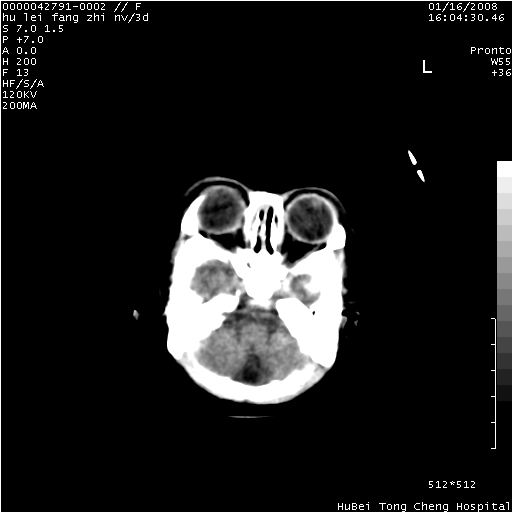

患儿 女,3天。惊跳,纳差。第二胎顺产,羊水ⅱ度。

临床诊断:hie?

颅脑ct轴位平扫(层厚、层距均为7mm),图像如下:

hie合并蛛网膜下腔出血

hie合并蛛网膜下腔出血,五、六脑室形成。

支持hie伴少量蛛血.

hie合并蛛网膜下腔出血。